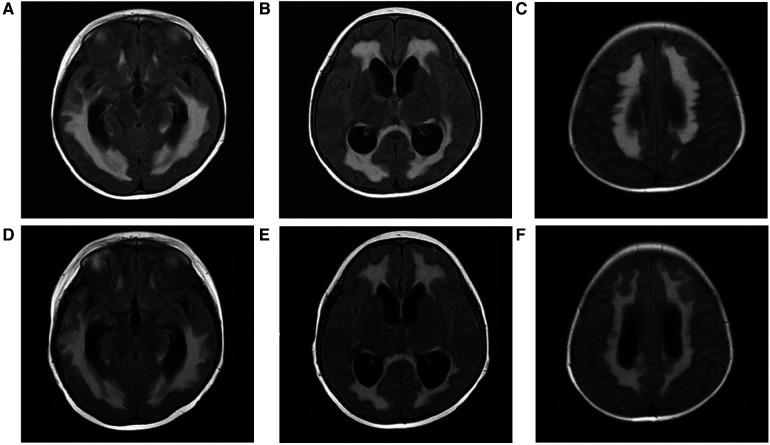

Lipopolysaccharide (LPS)-responsive beige ankyrin (LRBA) gene mutations were first reported as the cause of immunodeficiency syndromes and autoimmunity in 2012. The majority of LRBA patients have multiple organ system involvement and a complex clinical phenotype. Herein we present a comprehensive account on the disease progression and transplantation procedure in a patient with LRBA deficiency who exhibited progressive autoimmune disease symptoms along with recurrent pulmonary infections since the age of 6 years old. Despite receiving abatacept therapy and immunoglobulin replacement treatments to manage the symptoms, but the symptoms still progressed. Therefore, nine years after disease onset, patients were treated with allogeneic haematopoietic stem cell transplantation (allo-HSCT). The patient experienced acute and chronic graft-versus-host disease (GVHD) and recurrent infections after transplantation. During one and a half years of follow-up, we found that allogeneic haematopoietic stem cell transplantation can relieve the symptoms of autoimmune disease in patients with LRBA deficiency, and marked clinical improvement and recovery of immune function were observed following stem cell transplantation.

脂多糖(LPS)反应性米色锚蛋白(LRBA)基因突变于2012年首次被报道为免疫缺陷综合征和自身免疫的病因。大多数LRBA患者有多个器官系统受累及复杂的临床表型。在此,我们全面阐述了一名LRBA缺乏症患者的疾病进展和移植过程,该患者自6岁起就出现进行性自身免疫性疾病症状并伴有反复肺部感染。尽管接受了阿巴西普治疗和免疫球蛋白替代治疗以控制症状,但症状仍在进展。因此,在疾病发作9年后,患者接受了异基因造血干细胞移植(allo-HSCT)。患者在移植后经历了急性和慢性移植物抗宿主病(GVHD)及反复感染。在一年半的随访中,我们发现异基因造血干细胞移植可缓解LRBA缺乏症患者的自身免疫性疾病症状,干细胞移植后观察到明显的临床改善和免疫功能恢复。